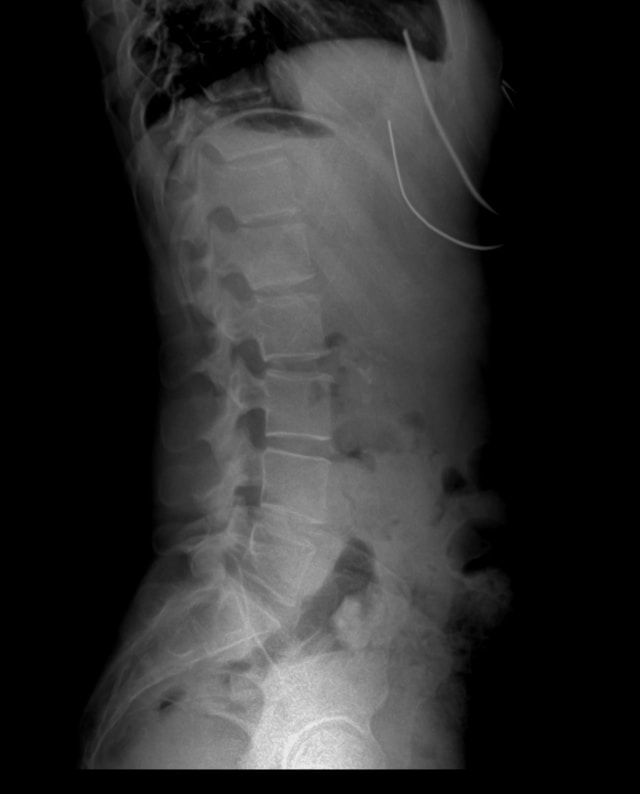

신바로정은 한방 병원에서 전통적으로 내려오던 관절 처방을 현대적으로 재정립한 전문의약품입니다. 수많은 약재 중 효과가 검증된 5가지 약초를 선별해 기초 연구, 전임상, 임상 시험을 모두 통과한 제품입니다. 주로 허리 디스크, 관절염, 근골격계 통증 치료에 처방됩니다.

두충은 뼈와 인대를 강화하고 허리와 무릎 통증에 오랫동안 사용되어 온 약재입니다. 신바로정에서 관절과 척추를 구조적으로 지지하는 역할을 합니다.